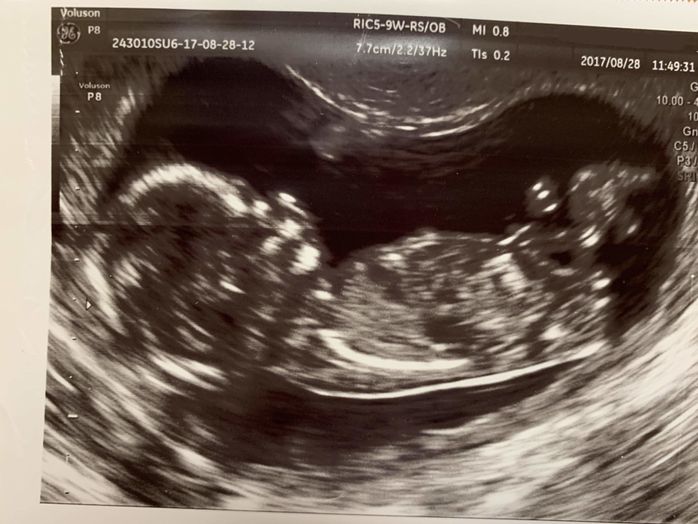

妊娠10週目 ぴこぴこ動くかわいらしい手と足

妊娠10週目。この頃には、つわりが始まっていました。不妊治療で授かった第1子、第2子のときもつわりで悩まされてきましたが、第3子のときが一番つらかった気がします。上の2人のお世話は、夫や実母に任せきりとなり、申し訳ないやら、情けないやら複雑な気持ちでした。ベッドで横になって過ごす毎日の心の支えは、母子手帳とマタニティマーク、そしてエコー写真の元気な姿の赤ちゃんでした。それをみて、「がんばろう!」という気持ちになっていました。

妊娠12週目 産院決定。初めての4Dも確認

妊娠12週目。上の子どもたちを出産した時と同じ大学病院での出産を希望したところ、人気があったために、初診まで1ヶ月もかかってしまいました。人気の産院はもっとかかるらしいことを聞いたことがあったので、無事に決定して一安心しました。この頃のエコー写真から、赤ちゃんの背骨や大腿骨などの大きな骨がしっかりと映るようになり、成長を実感できるようになりました。4Dエコーを見た夫が「この子は鼻筋がキレイ」と言っていました。早くも親バカです。